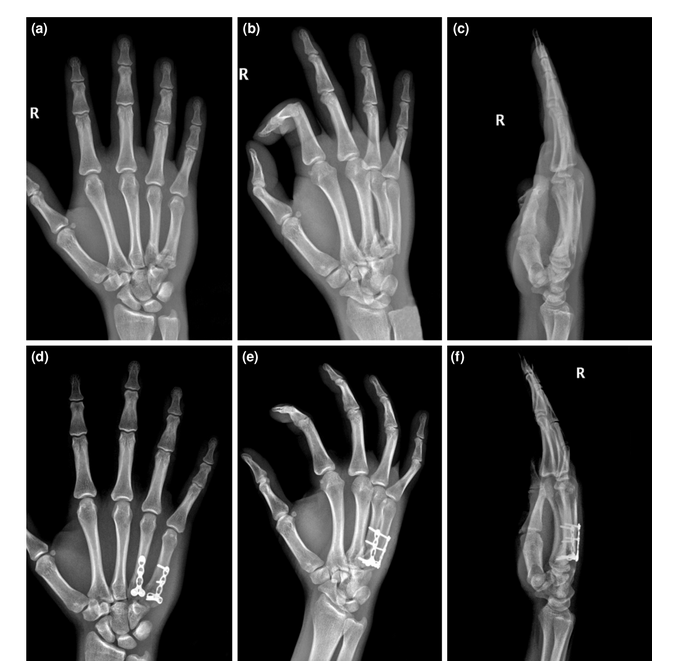

手术治疗患者的术前和术后影像;一个附加关节桥接k线钢板固定的例子。(a-c)术前AP、斜位和侧位x线图像。(d, e)术后AP和斜位x线图像。